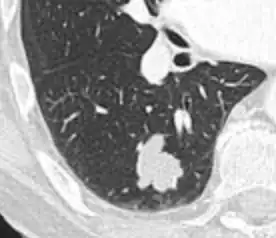

- In case of calcifications, a popcorn-like appearance indicates a hamartoma, which is benign.[3]

- In case of subsolid nodules, being part solid has a higher risk of cancer than being purely ground glass opacity.

-

Part solid nodule.[9] -

Ground glass opacity nodule.[9]